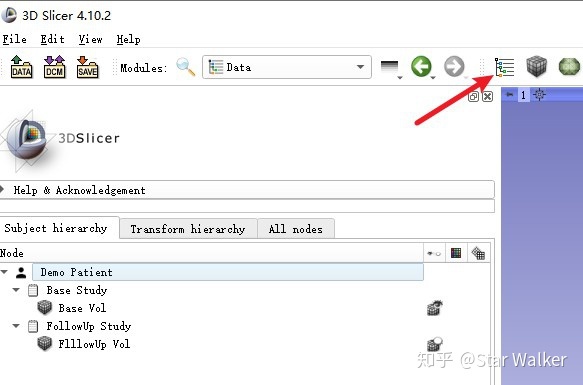

加载图像

这里省去图像加载的步骤,假定大家都已经加载了需要配准的图像。注意,需要有2个Volume数据,或者是两组能够生成三维Volume的扫描序列。一般来讲,这2个Volume或序列,是同一患者的大致相同身体部位,在不同时期接受的两次扫描,可以是相同类型的扫描设备,比如两个都是CT,也可以是不同类型的扫描设备,比如一个是CT、一个是MR。

因为手边正好有同一患者的两次CT扫描数据,所以咱们这里选择两个CT Volumue的配准,作为例子。

数据加载进来后,为了便于区分,咱们进入Data模块,把两个Volume更改一下名称。选择检查时间较早的Volume,改名为“Base Vol";选择检查时间较晚的Volume,改名为“FollowUp Vol”。操作要点如下图。